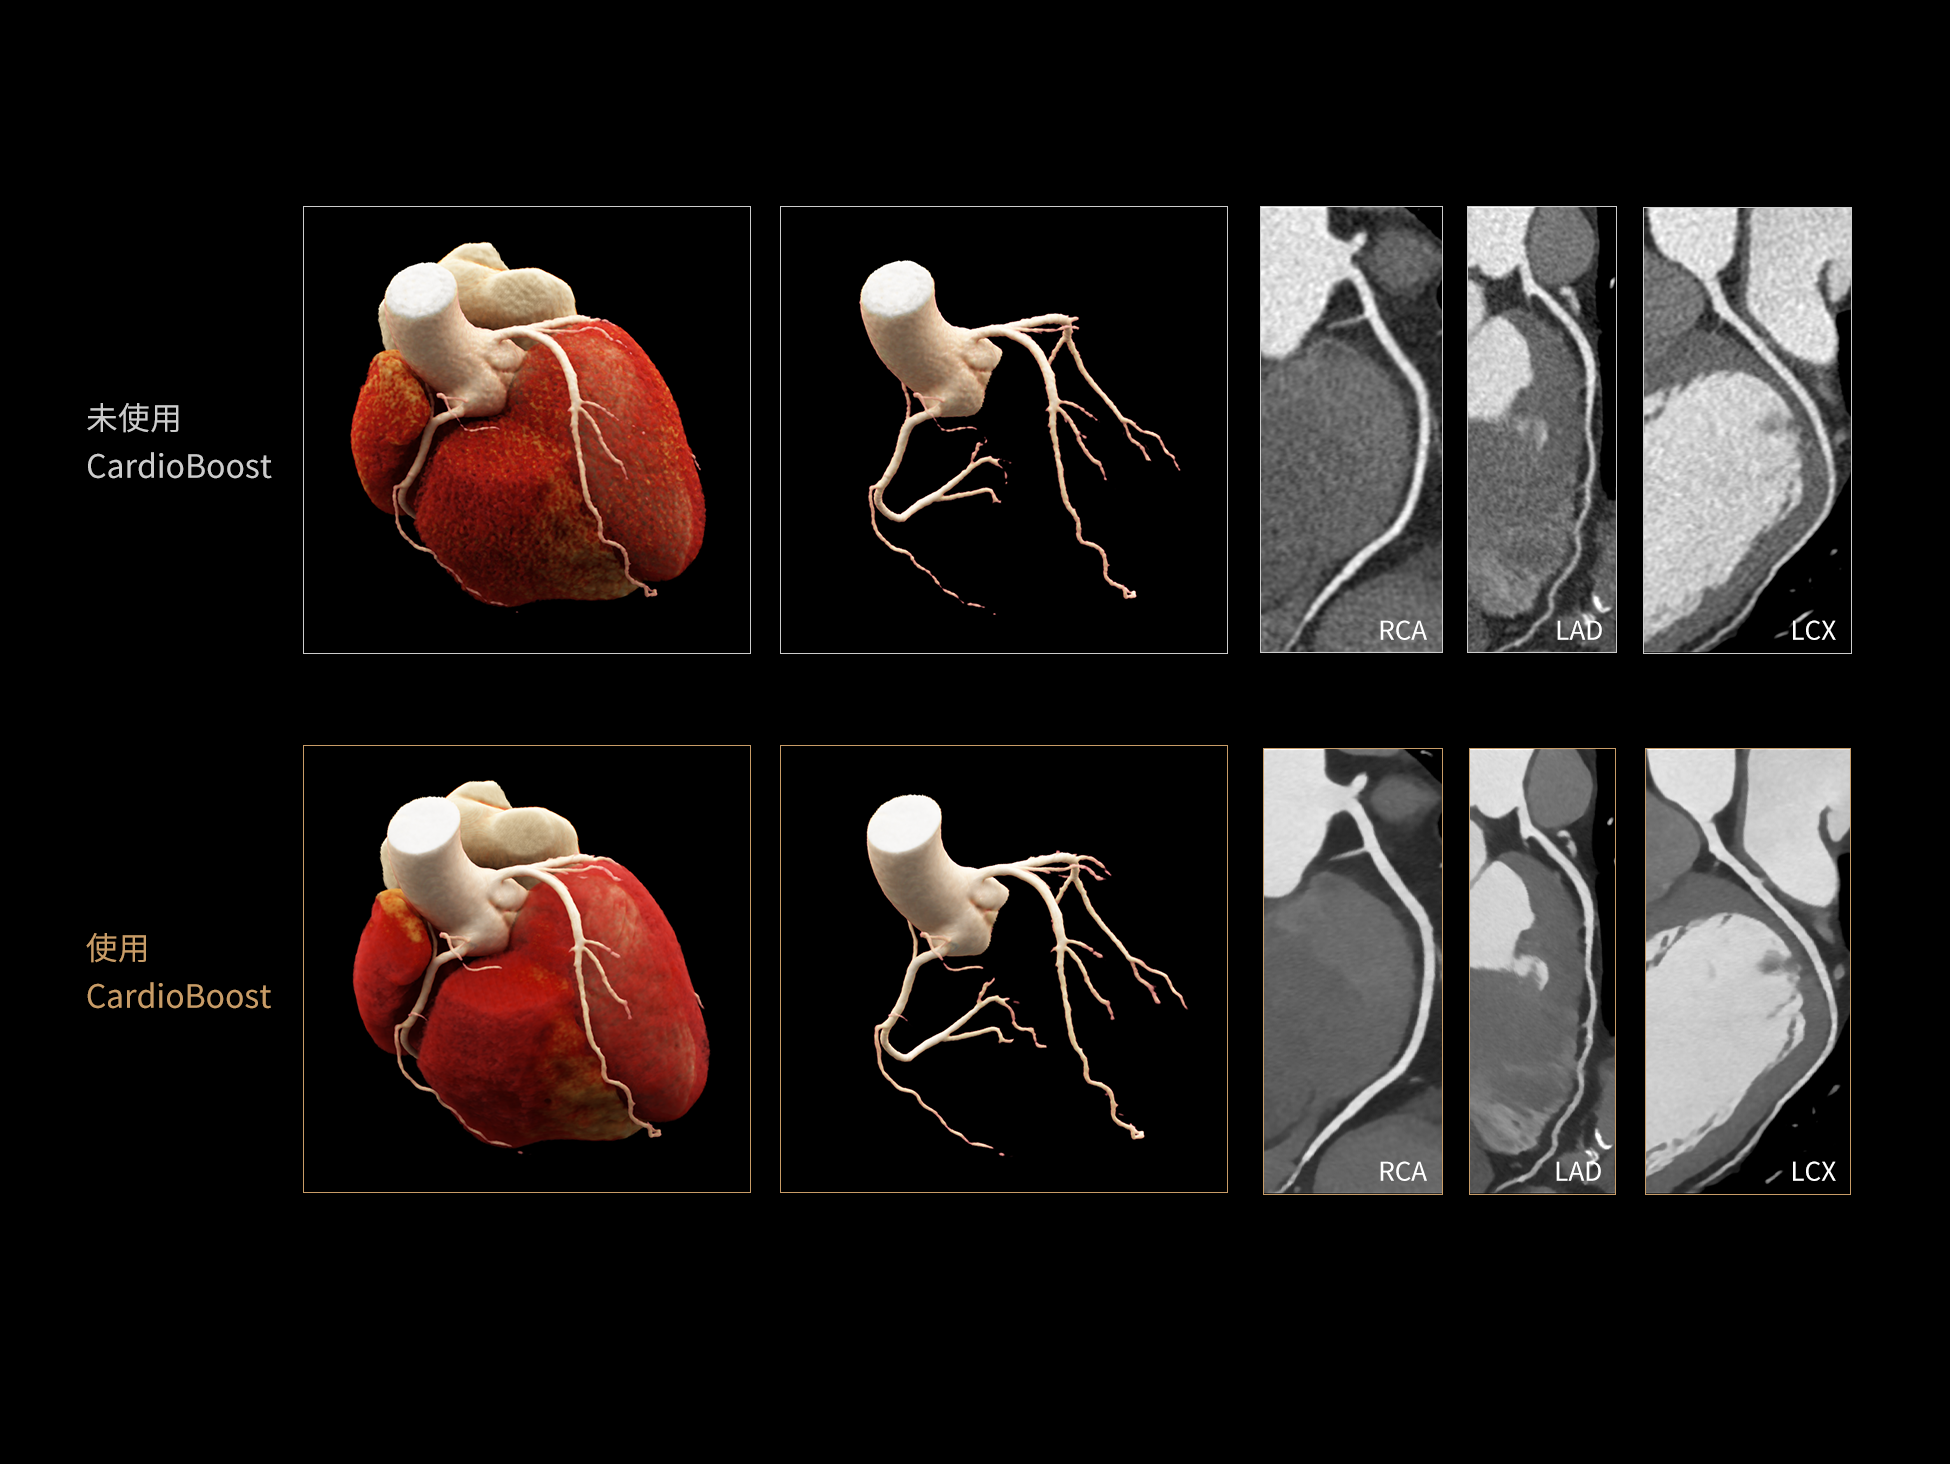

低对比度分辨率提升

空间分辨率提升